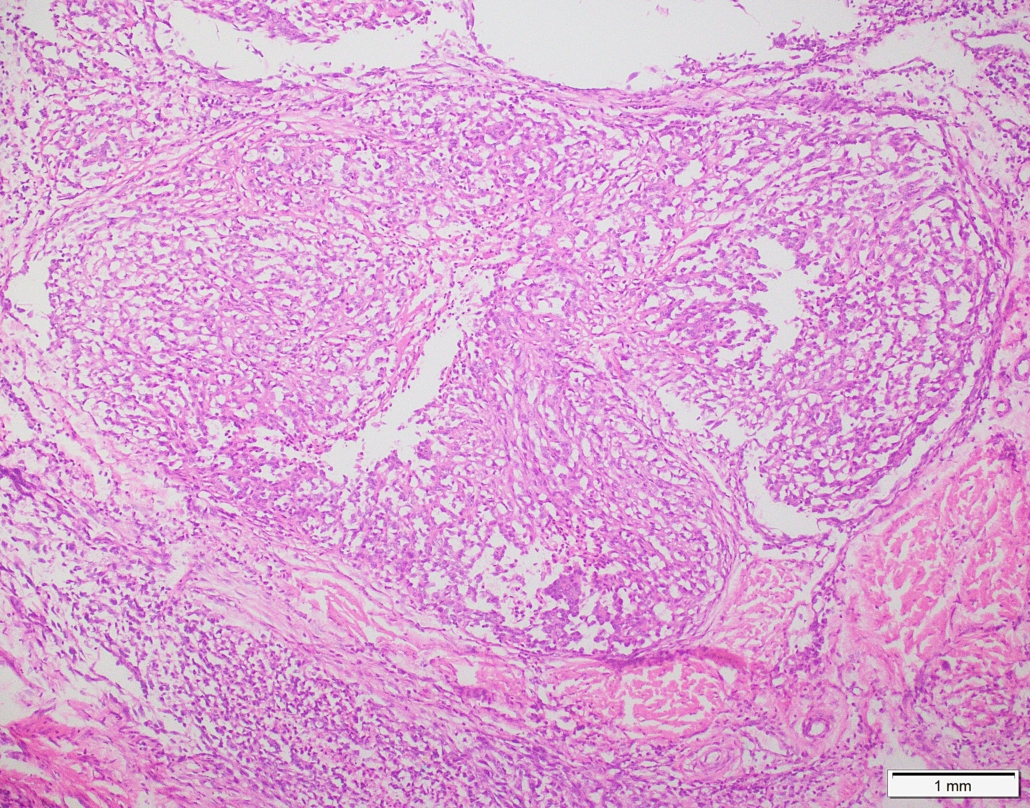

Case 03

Case presented by Dr Shaarif Bashir, FCPS (PAK), Shaukat Khanum Memorial Cancer Hospital and Reserach Centre, Pakistan